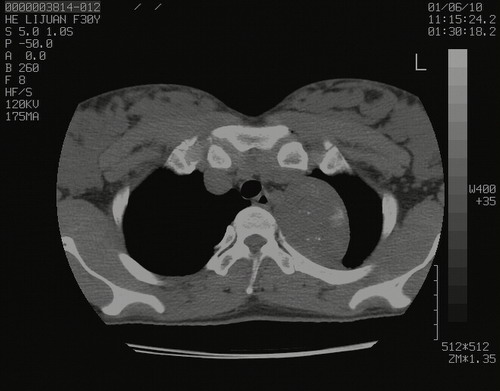

怀孕3个月时(2009-3至4月间),自述突感左侧前后胸疼痛1天,以前胸明显,随后偶感闷痛,余未见异

左肺尖脊柱旁沟肿块,境界清楚,边缘光滑,密度不均,内有多发点片状钙化,考虑良性肿瘤,骨软骨瘤或神经源性肿瘤可能,肺错构瘤不除外。

左后上纵隔见一类圆形肿块影,外侧边界清,密度不均匀,内可见点状钙化影,增强呈不均匀强化,考虑神经源性肿瘤可能。期待病理结果。